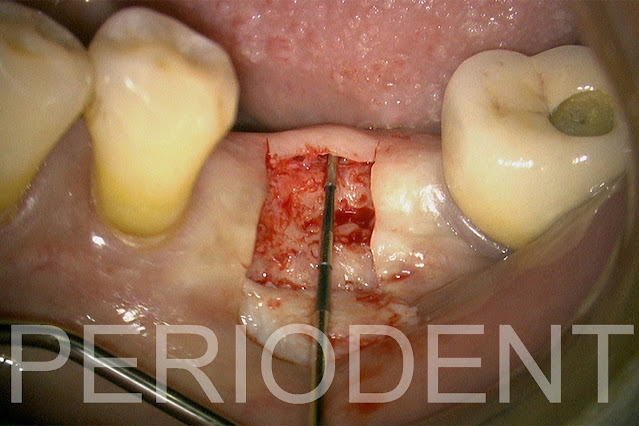

8. 拔除第一大臼齒並同時補骨,先切開牙根,再拔除

9. 補骨影片